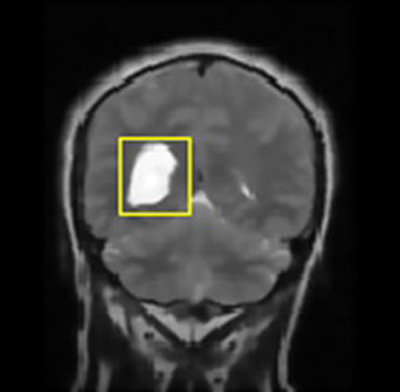

- Step-6: Image classification was done to differentiate cancerous and non-cancerous cells from the brain image using sorting factor kappa and properties of images that are shown through the bounding box.

In this way, a boundary box differentiates the regions of image with dissimilar properties in few seconds that further lead to the exact position marking of cancer pertaining in the brain and further extracts out the cancerous portion out of the MRI image fed as an input.